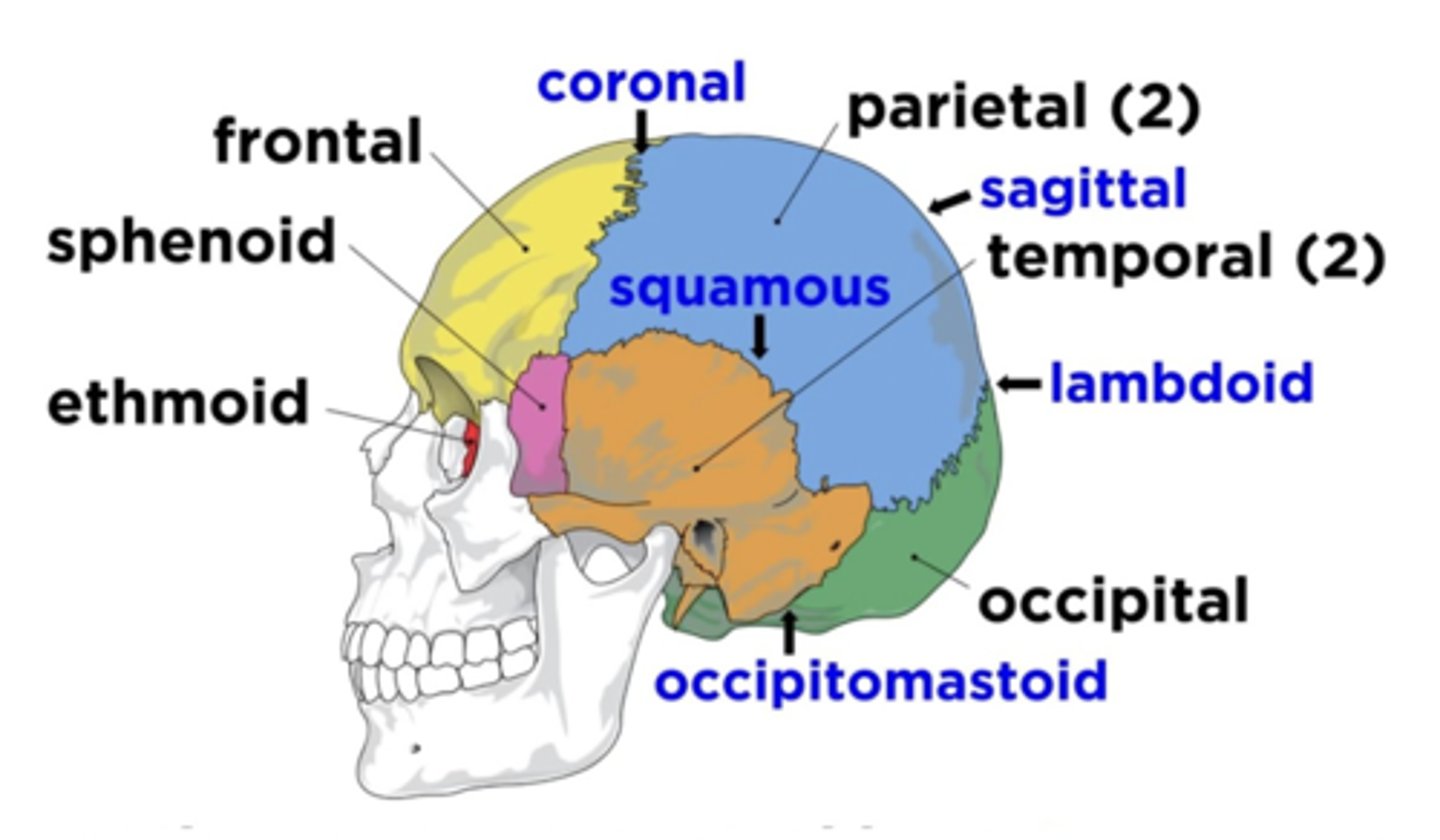

Cranial Bones (8)

- Ethmoid

- Frontal

- Sphenoid

- Temporal (2)

- Occipital

- Parietal (2)

(EFSTOP)

Ethmoid Bone

Forms part of the posterior portion of the nose, the orbit, and the floor of the cranium (red)

Frontal Bone

Bone that forms the forehead (yellow)

Sphenoid Bone

Forms part of the base of the skull and parts of the floor and sides of the orbit (pink)

Temporal Bone (2)

Bone that forms parts of the side of the skull and floor of the cranial activity (orange)

Occipital Bone

Bone that forms the back of the head (green)

Parietal Bone (2)

Either of two skull bones between the frontal and occipital bones and forming the top and sides of the cranium (blue)

4 Main Sutures of the Skull

- Saggital

- Lamboid

- Coronal

- Squamous

(SLCS)

Saggital Suture

Suture that separates the left and right parietal bone

Lamboid Suture

Suture between the occipital and parietal bones

Coronal Suture

Suture between the parietal and frontal bones of the skull

Squamous Suture

Suture between parietal and temporal bones